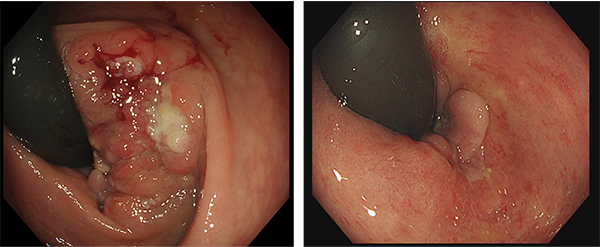

ロボット支援下手術により安全に吻合できるようになったため人工肛門が回避できた。

ロボット支援下手術では、高画質3D立体的映像のもとで手術を行うため、腹腔鏡下手術の欠点であった遠近感覚が改善されます。また、使用する鉗子類は人間の手よりも広い可動域を持ち、複雑かつ繊細な動きが可能なため、術者の指先の動きを明確に再現することができます。なおかつ手振れ防止機能も有するため、従来の腹腔鏡下手術よりもさらに正確な手術を行うことが可能です。さらに、ダビンチXiサージカルシステムに内蔵された蛍光内視鏡の赤外線蛍光波長で臓器を観察すると、血液の流れ具合を確認することができます(図8)。この機能を使って血流が豊富な部分で腸管をつなぎ合わせると縫合不全の発生率が低下することが報告されており、人工肛門を回避しやすくなると考えています。